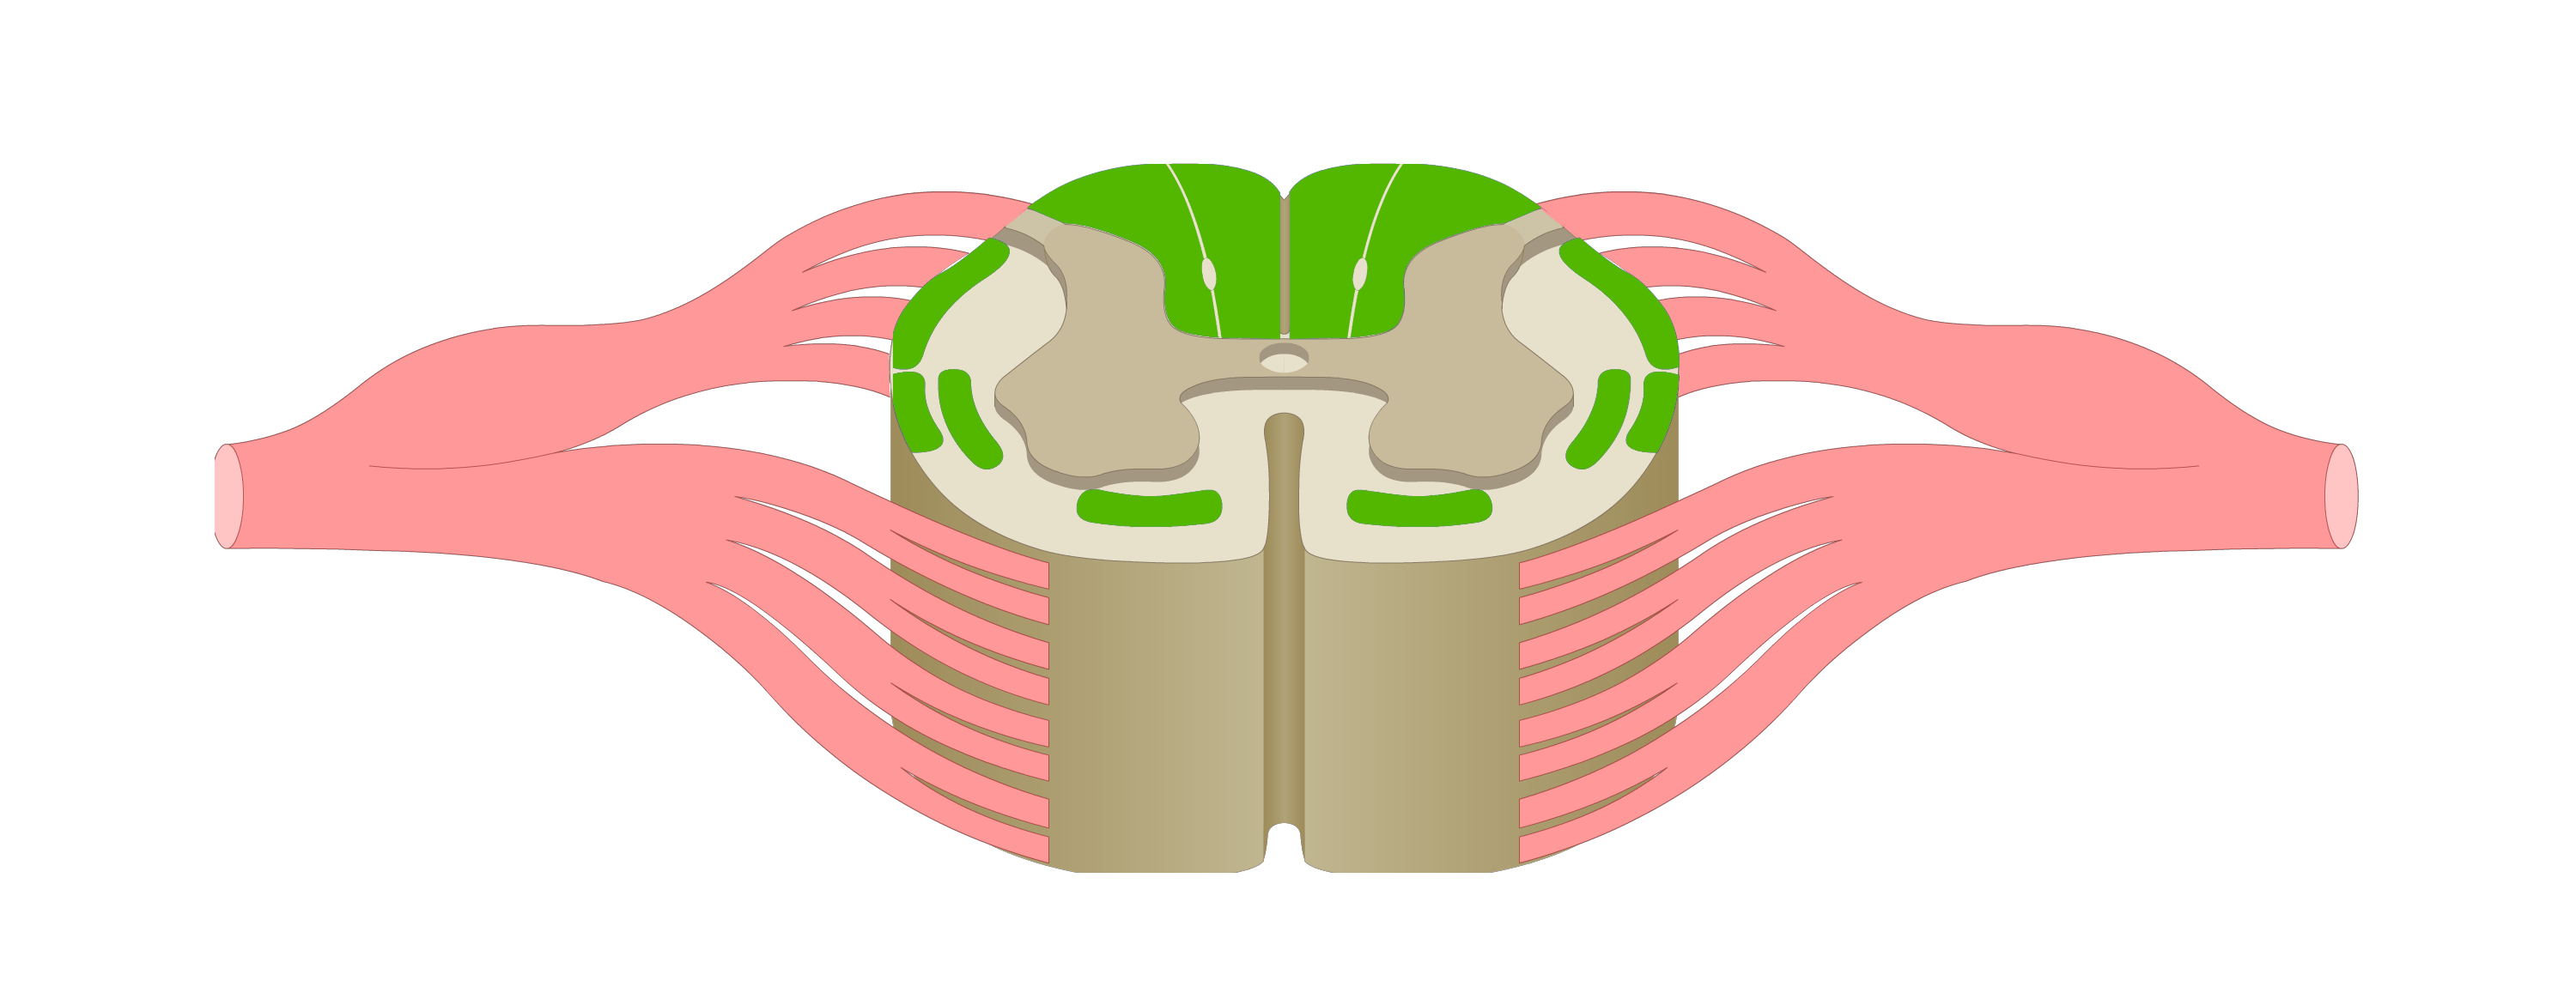

motor tracts

sensory tracts

dorsal root ganglion

dorsal horn

lateral horn

ventral horn

dorsal funiculus

lateral funiculus

ventral funiculus

central canal

ventral median fissure

dorsal median sulcus